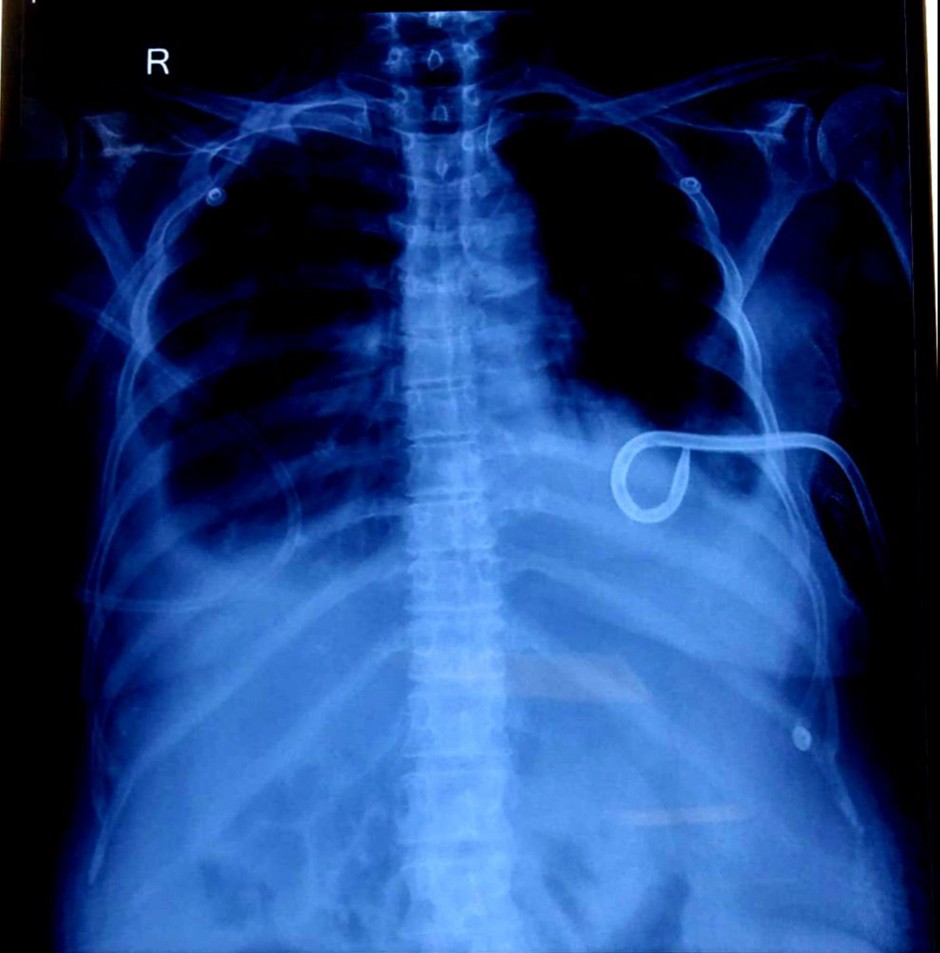

- Chest X-ray AP (June 9, 2025, and June 11, 2025): Both radiographs consistently demonstrated the presence of significant pleural effusion, correlating with her respiratory symptoms.

Prior to the current admission, she had undergone a pigtail catheter insertion on June 9th, 2025, at 7:00 PM, for the management of refractory ascites. Drain outputs after this procedure were substantial: 1200 ml on June 10th, 2025, and 465 ml on June 11th, 2025. A unit of Packed Red Blood Cells (PRBC) was transfused on June 10th, 2025, to address anaemia. She had a long-standing history of abdominal distension, with a recorded maximum girth of 92 cm, for which recurrent ascitic tapping had been performed. Despite recommendations for systemic chemotherapy, the patient had previously opted to decline active oncological treatment, indicating a preference for palliative and symptomatic management.